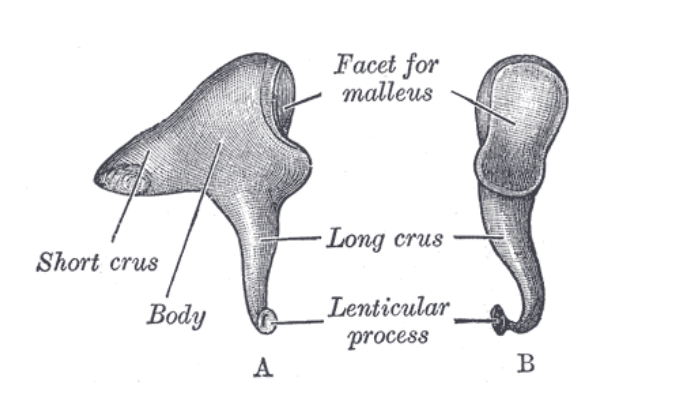

The Incus

The Incus

Body of the incus

Short crus of the incus

Long crus of the incus